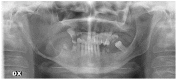

Mandibular Reconstruction after Resection of Ameloblastoma by Custom-Made CAD/CAM Mandibular Titanium Prosthesis: Two Case Reports, Finite Element Analysis and Discussion of the Technique

Virtual surgical planning for CAD/CAM mandibular reconstruction by titanium prosthesis was recently reported for resected cases. Even if some advantages are evident, difficulties that may arise for TMJ function after reconstruction originate from prosthesis contamination through oral mucosa dehiscence. In these two cases reported of mandibular reconstruction after resection of ameloblastoma by custom-made CAD/CAM titanium prosthesis, the procedures were aimed to preserve the TMJ glenoid cavity and articular disc avoiding functional problems for hemi-mandibular resections that included the condyle (as in case #1) or with condylar preservation (as in case #2) and avoiding intraoral incisions in both cases. The entire surgical planning and prosthetic fabrication were explained with specifications and the sequence of the surgical procedure. Finite elements analysis (FEA) was performed to check the force distribution and efficacy of the prosthetic device (case 1 with hemi-mandibular resection and rehabilitation). Although successful in these two cases, surgical reconstruction of the mandibular defect after resection by a CAD-CAM custom-made prosthesis still shows some drawbacks and failure risks. Several advantages of this technique and the surgical success in these two cases were presented, but limitations and side effects must be considered when cases are selected.